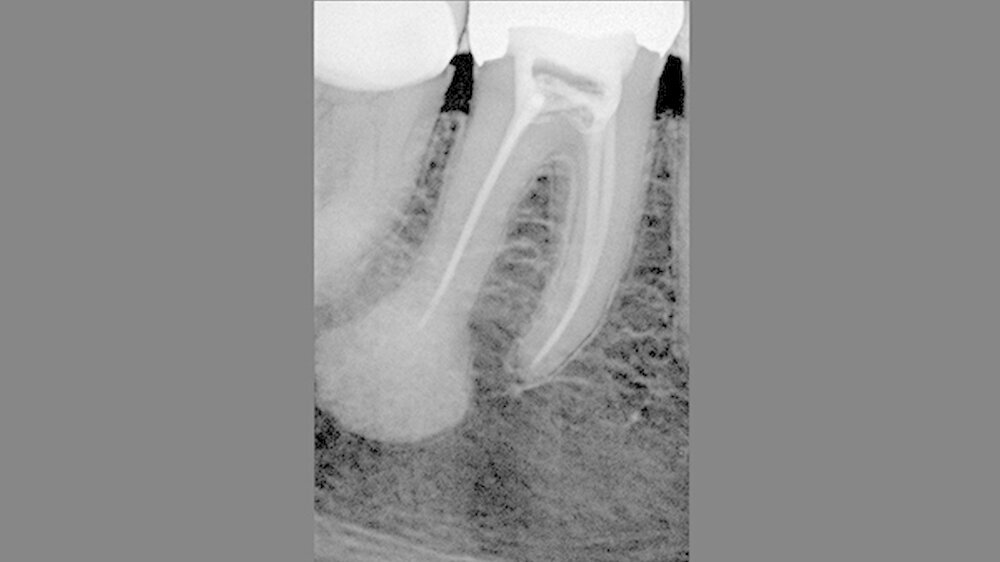

Aufgrund des Eingriffs war eine Vitalerhaltung des Zahns nicht möglich. So führten wir nach Zustimmung der Patientin präoperativ am 26.8.2015 eine endodontische Behandlung durch. Die beiden mesialen Wurzelkanäle enthielten eine vitale gesunde Wurzelpulpa, die beiden distalen Kanäle waren stark obliteriert und zeigten ein avitales und mazeriertes Pulpagewebe.